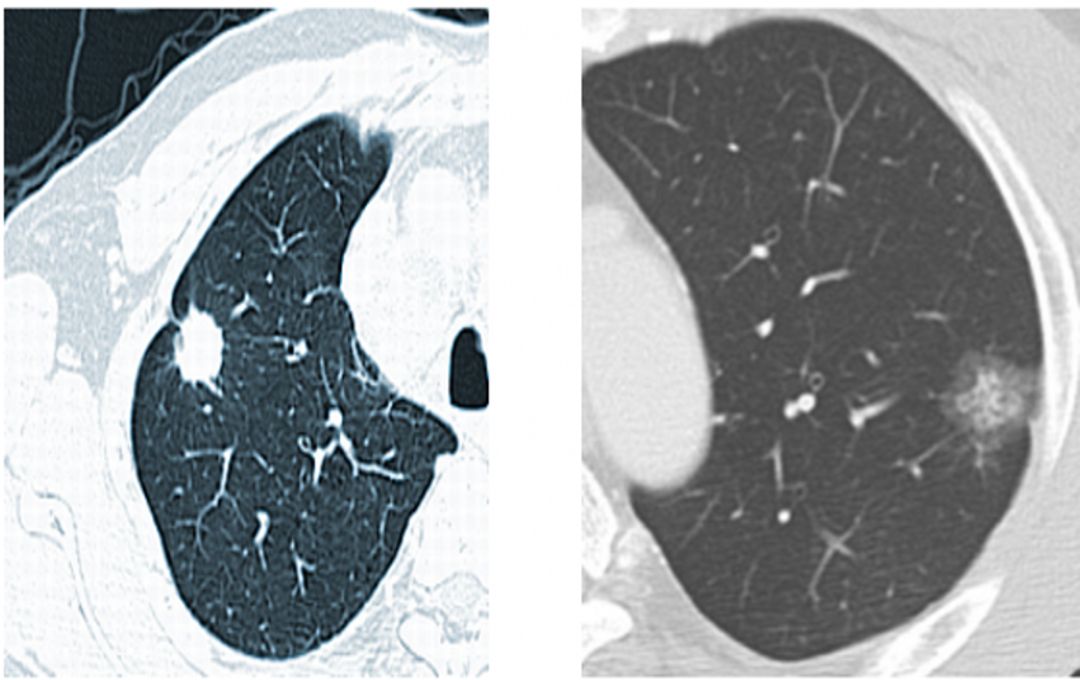

肺结节,是影像学上的一个描述性名词,指的是病灶的大小和形态,而不是病灶的性质。在CT或胸片检查中,发现肺部类圆形的病灶:直径小于3cm的通常被称为结节灶,直径小于1cm的被称为“小结节”,而直径小于0.5cm时就被描述成微小或细小结节。

根据结节的密度不同,可以分为纯磨玻璃结节、部分实性磨玻璃结节和纯实性结节。